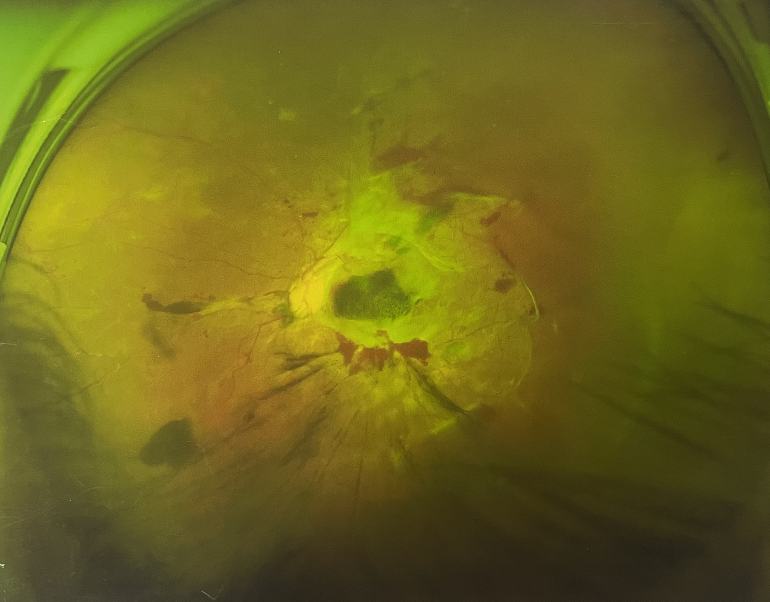

眼底出血一般多久能好?眼底出血可以由眼科本身疾病引起,常見的是視網(wǎng)膜靜脈阻塞、糖尿病視網(wǎng)膜病變、中心性滲出性視網(wǎng)膜病變、視網(wǎng)膜動脈硬化、老年性黃斑病變、視網(wǎng)膜靜脈周圍炎。

另外,眼底出血還可以由全身疾病引起,比如糖尿病可以引起眼底出血,高血壓也會引起眼底出血,還有嚴(yán)重的腎病,血液方面的疾病都可以導(dǎo)致眼底出血。

眼底出血一般多久能好?眼底出血如果是輕癥,時間較短的患者大約3-6個月可以恢復(fù),如果是重癥或者病程較長的患者,可能要持續(xù)1年,甚至2年時間。

眼底出血一般多久能好?眼底出血是醫(yī)生用檢眼鏡才能看到,患者和其他人看不見。眼底出血不是單獨(dú)的病,一般來說是由眼科本身疾病造成,還可以由全身疾病造成。比如常見的視網(wǎng)膜靜脈阻塞、糖尿病視網(wǎng)膜病變等引起的眼底出血較常見。眼底出血一般多久能好?所以眼底出血的出血吸收時間也不一樣,要根據(jù)病情輕重決定其預(yù)后,出血吸收時間也不一樣。